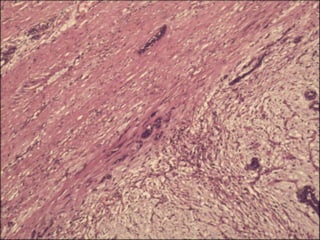

Borderline phyllodes tumor.

The stroma is moderately cellular and the stromal cells show

moderate nuclear atypia

(hematoxylin-eosin,